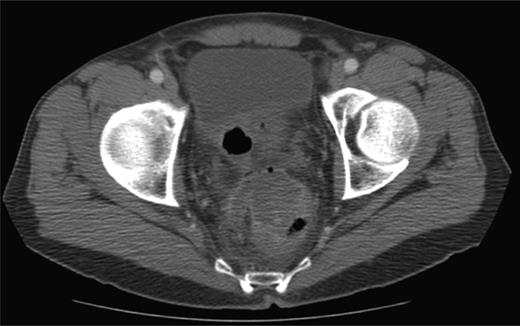

In the 6-week follow-up, repeat CT demonstrated eccentric thickening of the rectosigmoid with interval development of an adjacent complex pelvic fluid collection with supralevator extension measuring 3.5 × 2.5 cm (Fig. 2a and b). Percutaneous needle biopsy revealed pus, and a drainage catheter was left in place (Fig. 3a and b). The patient did not improve, was reimaged and was found to have collection extending into the ischiorectal fossa and supralevator space (Fig. 4). Owing to refractory pain and persistent leukocytosis, the patient was taken to the operating room for examination under anesthesia. No fistulous tract or internal drainage was noted within the rectal vault; however, consistent with the imaging, external induration was observed along the right ischiorectal fossa, where, upon incision, a large purulent cavity was evacuated. On evening rounds, the patient was noted to have a marked leukocytosis and frank stool coming from the ischial wound, and he was taken emergently to the operating room for diagnostic laparotomy where a perforated diverticulum adherent to the pelvic sidewall was identified (Fig. 5). Therefore, a Hartmann procedure, drainage of supralevator abscess, irrigation and debridement of the right ischiorectal wound, was performed.

(a) CT-guided percutaneous drainage of perirectal abscess (b) fluoroscopic drain study showing contrast extending into the supralevator space.